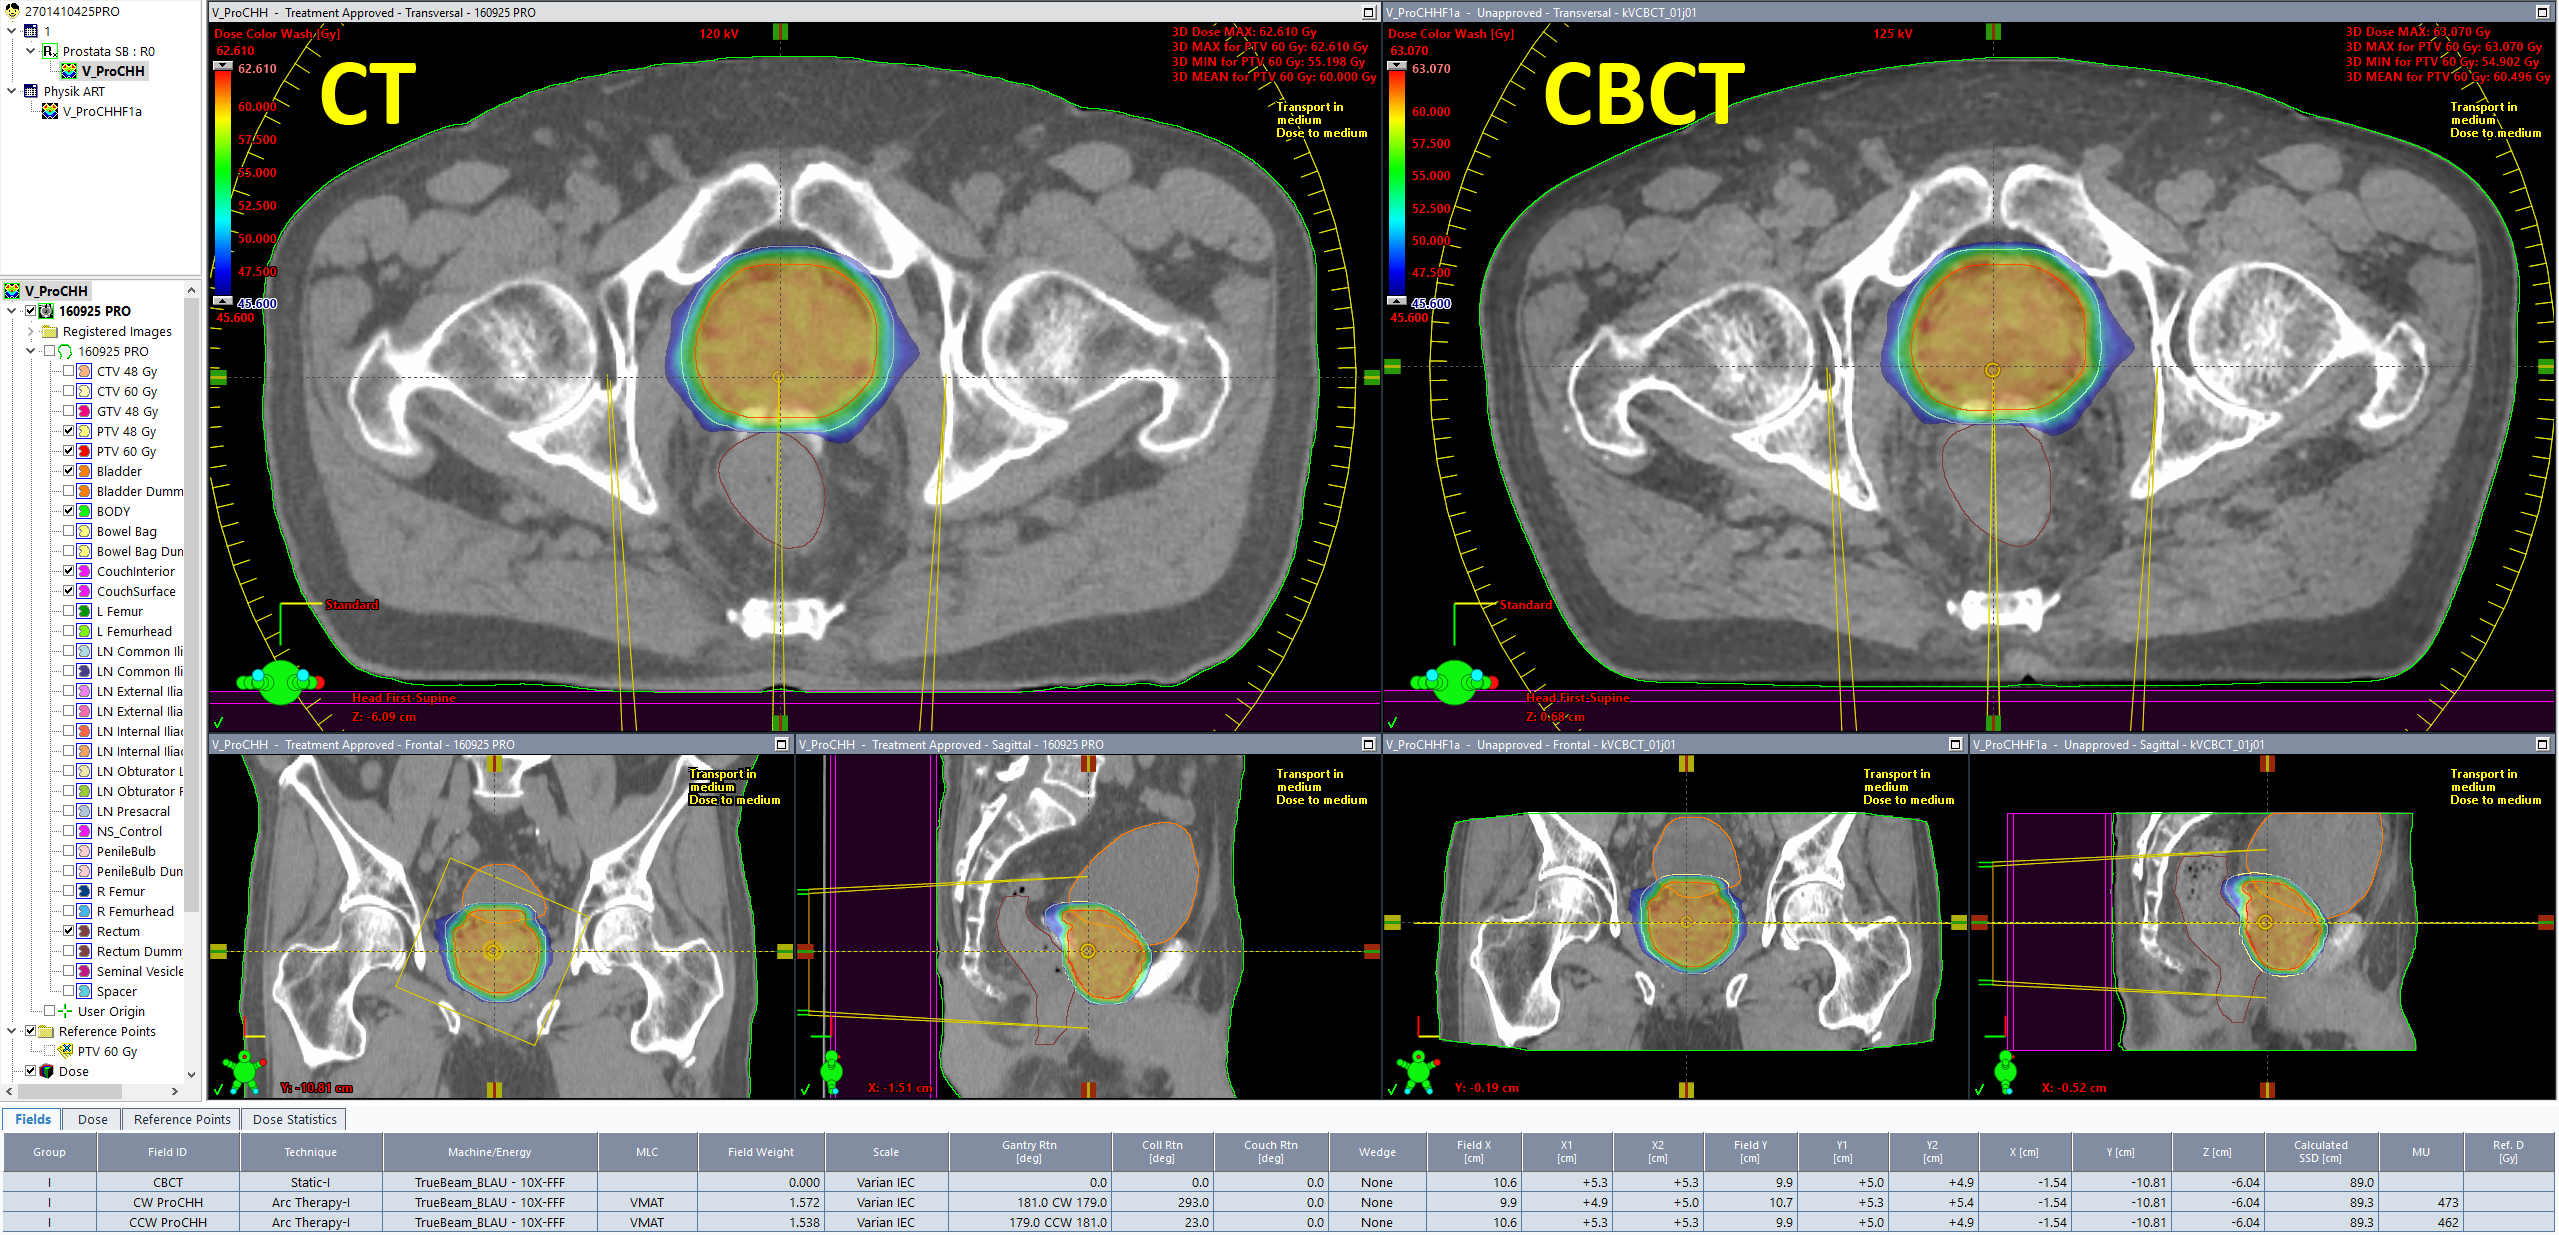

The patient anatomy shown in the first image belongs to a prostate plan with the CHHiP prescription 20 x 3 Gy = 60 Gy to the (central) high dose region, 48 Gy to the periphery. The hydrogel which was used to push the rectum away from the high dose region is also visible.

During the first session, we asked the therapists to aquire a Pelvis scan instead of the Spotlight they would normally choose. During CBCT aquisition, the PerfectPitch couch is always levelled (Pitch = Roll = 0.0°). Then an online match against the planning CT is performed, followed by a 6 DoF couch shift, followed by the treatment.

The elegance of the integrated Varian system is that as soon as the treatment session on the TrueBeam is closed, the CBCT image can be opened on any Eclipse workstation on the network (no export). Immediately after the treatment, we performed the following steps in order to get dose calculated on today's CBCT:

Dose on the CBCT is calculated with the same parameters as in the treatment approved plan (AXB, 2mm grid). Since the patient had no metal implants, we skipped the "Segment High Density Artifacts" step in Contouring. Consequently, no material assignment was necessary.

From here, it would be easy to walk a few steps further down the road, fire up the Photon Optimizer (PO) in Eclipse and reoptimize the CBCT plan based on today's anatomy. Since PO and AXB use the GPU for both optimization and dose calculation, this would probably take another two or three minutes, but without compromises in accuracy, because the same optimization and dose calculation settings can be used as in the original plan. And bulk-density overrides are definitely not required.